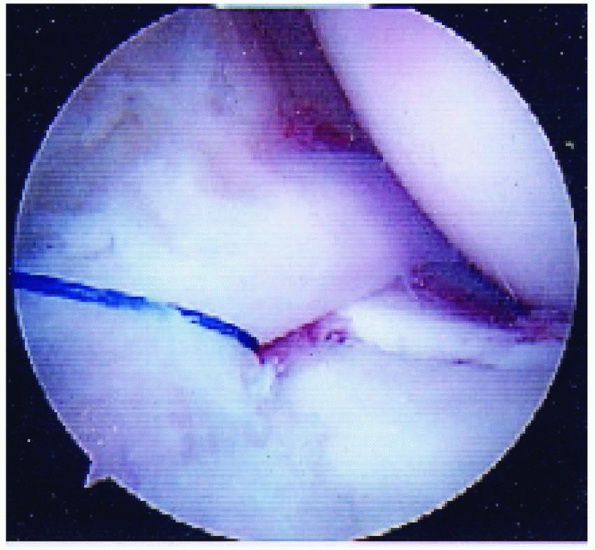

displaced tibial eminence fragment has been reported and may be a

rationale for considering arthroscopic or open reduction in displaced

tibial spine fractures (Fig. 24-5).54,59,94,177

Meniscal entrapment prevents anatomic reduction of the tibial spine

fragment, which may result in increased anterior laxity or a block to

extension.120,148,211,236,240 Furthermore, meniscal entrapment itself may cause knee pain after fracture healing.59 Falstie-Jensen and Sondergard Petersen,94 Burstein and colleagues,54 and Chandler and Miller59

have all reported cases of meniscal incarceration blocking reduction of

type 2 or 3 tibial spine fractures in children. The prevalence of

meniscal entrapment in tibial spine fractures may be common for

displaced fractures. As aforementioned, the anterior horn of the

lateral meniscus typically remains attached to the tibial eminence

fracture fragment. However, the anterior horn of the medial meniscus or

the intermeniscal ligament may become incarcerated. Mah and colleagues200

found medial meniscal entrapment preventing reduction in 8 of 10

children with type 3 fractures undergoing arthroscopic management. In a

consecutive series of 80 skeletally immature patients who underwent

surgical fixation of hinged or displaced tibial eminence fractures

which did not reduce in extension, Kocher et al.177

found entrapment of the anterior horn medial meniscus (n = 36),

intermeniscal ligament (n = 6), or anterior horn lateral meniscus (n =

1) in 26% (6/23) of hinged (type 2) fractures and 65% (37/57) of

displaced (type 3) fractures. The entrapped meniscus can typically be

extracted with an arthroscopic probe and retracted with a retaining

suture (Fig. 24-6).

FIGURE 24-6 Retraction of an entrapped anterior horn medial meniscus using a retaining suture.